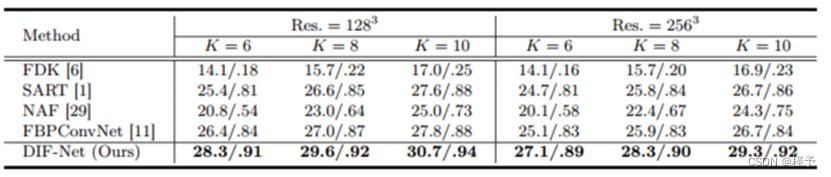

性能。如表1所示,我们在不同输出分辨率的重建设置下比较了DIF-Net与之前的四种方法[1,6,22,29](即,1283、2563)以及来自不同数量的投影视图的投影视图实验表明,我们提出的DIF-Net即使只使用6个投影视图也可以重建具有高图像质量的CBCT,其在PSNR和SSIM值方面明显优于先前的工作。更重要的是,DIF-Net可以直接应用于重建具有不同输出分辨率的CT图像,而不需要模型重新训练或修改。如图3所示的视觉结果,FDK [6]由于缺乏足够的投影视图而产生具有许多条纹伪影的结果; SART [1]和NAF [29]产生具有良好形状轮廓的结果,但缺乏详细的内部信息; FBPConvNet [11]重建了良好的形状和中等的细节,但仍然存在一些条纹伪影;我们提出的DIF-Net可以重建出高质量的CT图像,具有更好的形状轮廓、更清晰的内部信息和更少的伪影。2补充资料中给出了输入视图数量的更直观的比较。

表1.在PSNR(dB)和SSIM测量下,DIF-Net与先前方法的比较。我们评估了不同输出分辨率(Res.)和不同投影视图数(K)的重建。